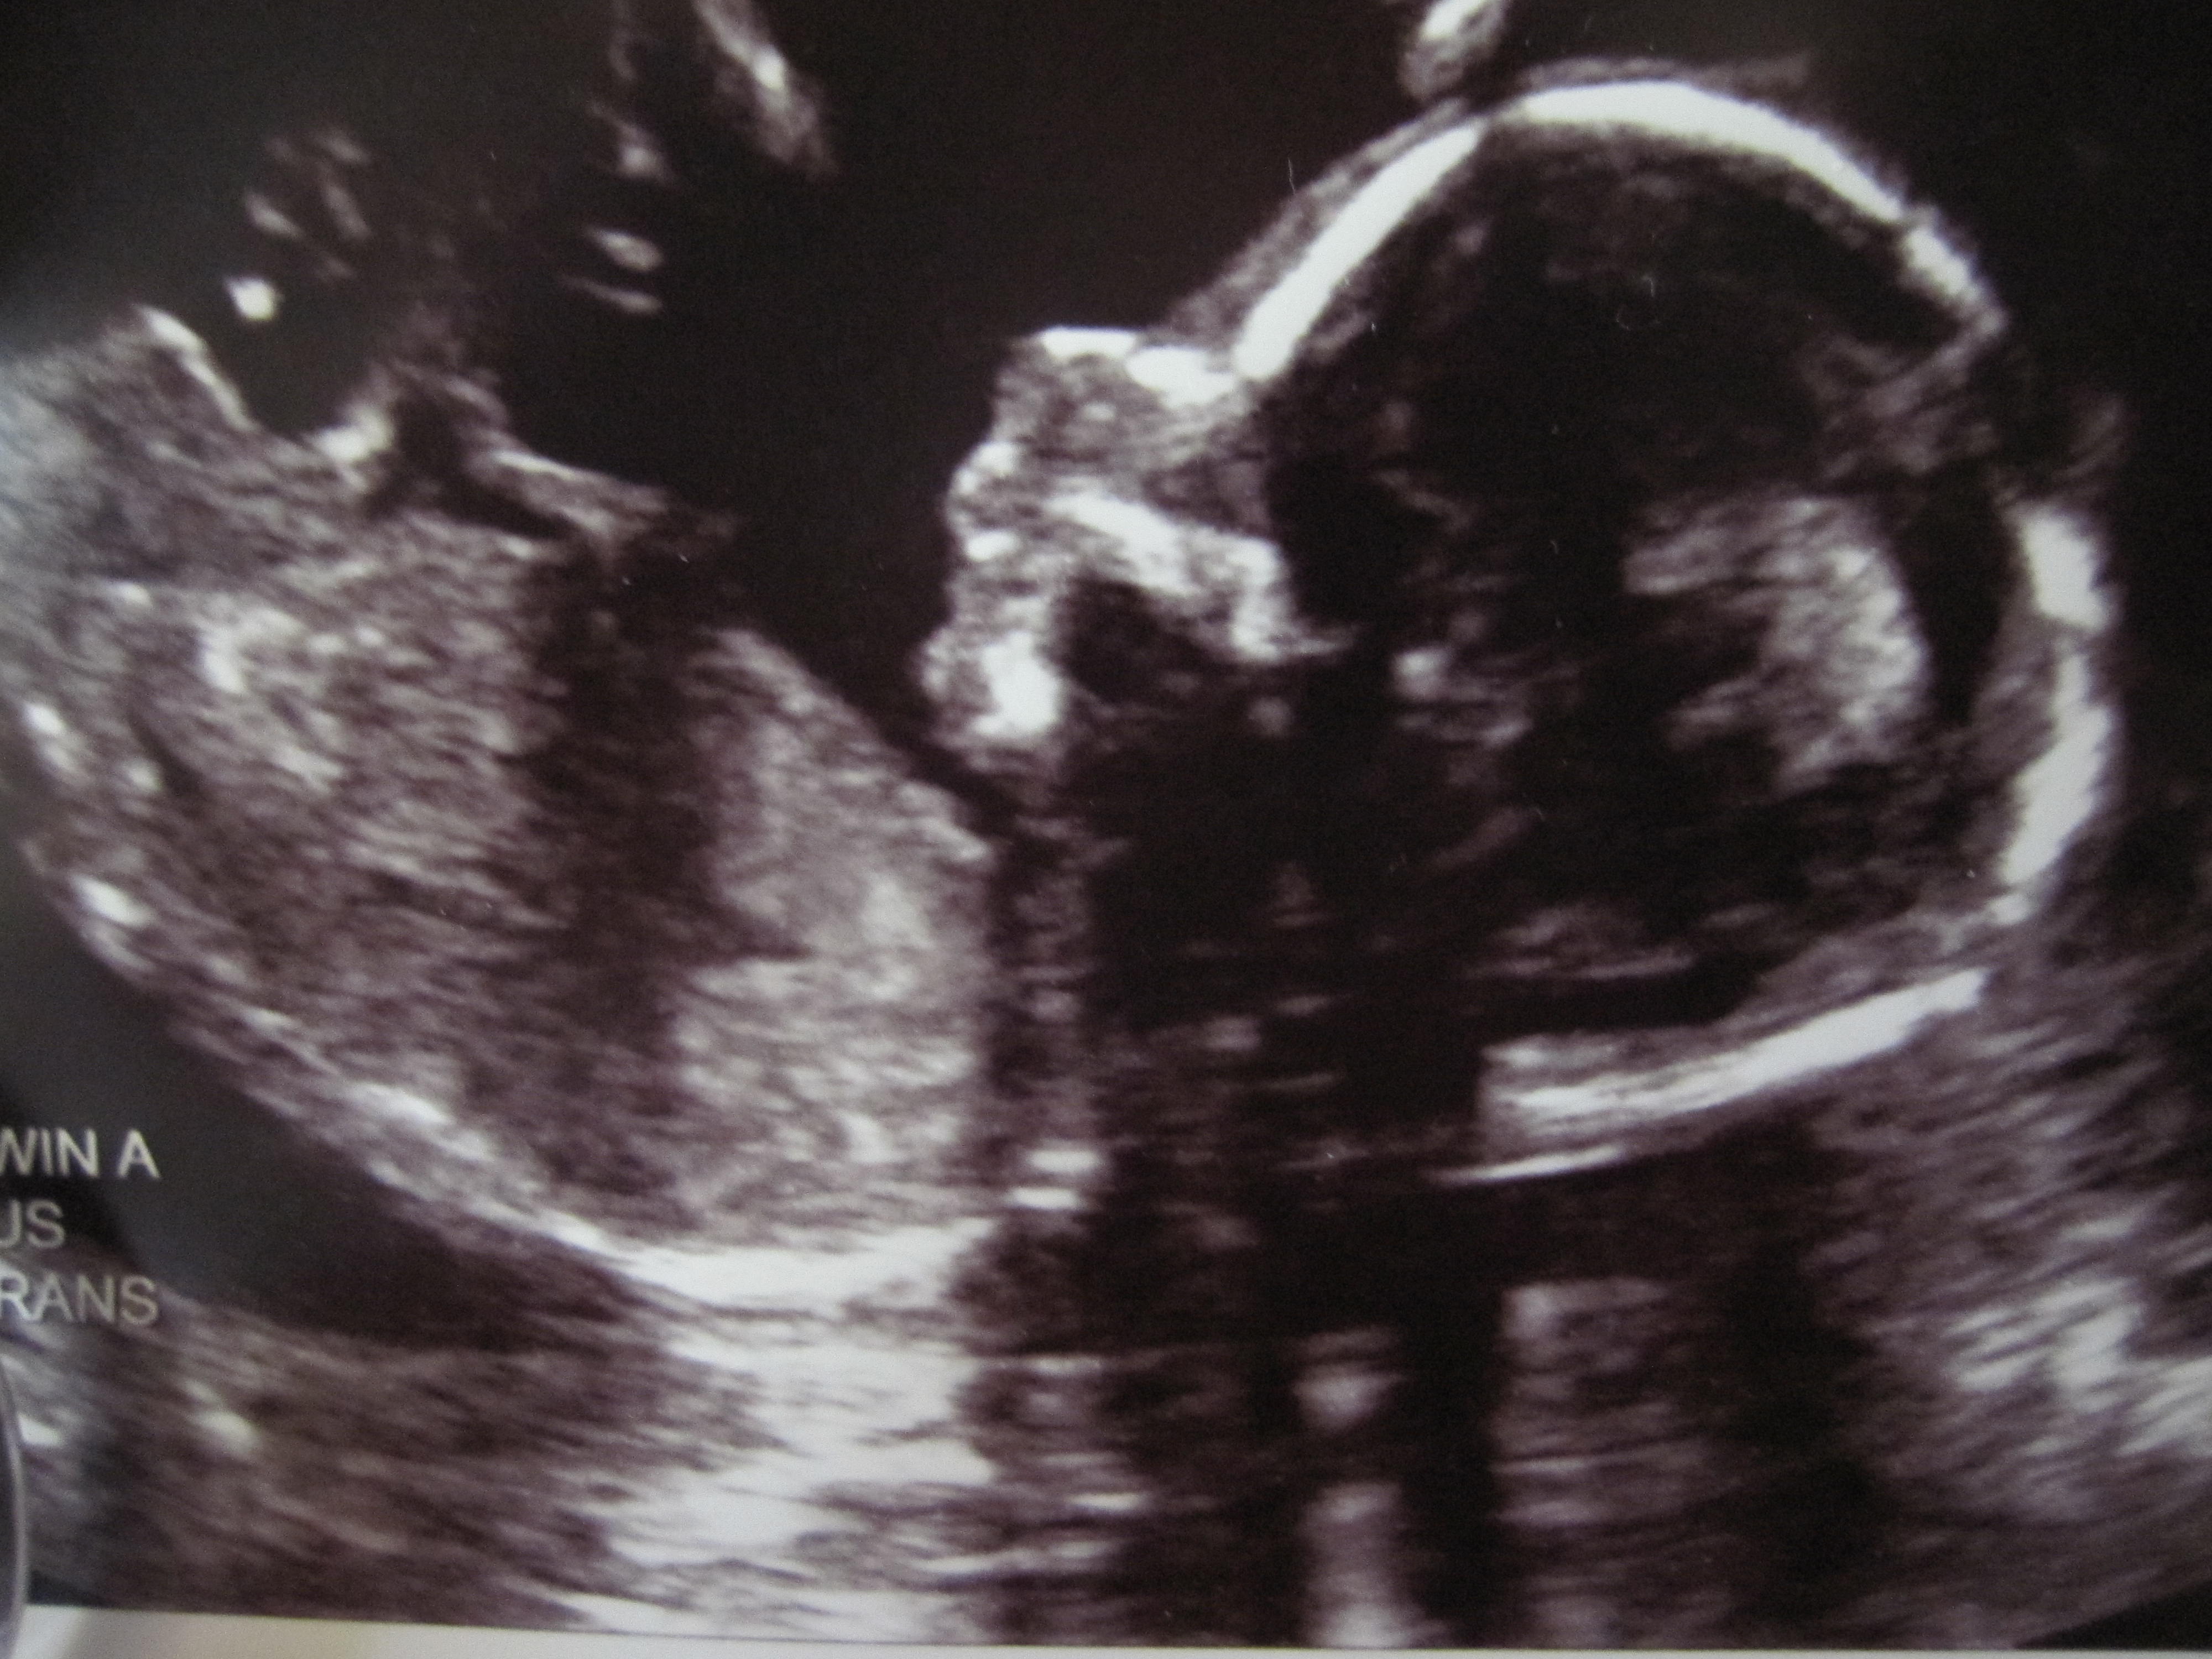

If you look closely, you can see she is smiling. (Baby B, 18wks)

Baby A at 18wks. Looking closely here you can see the umbilical chord. So cool.